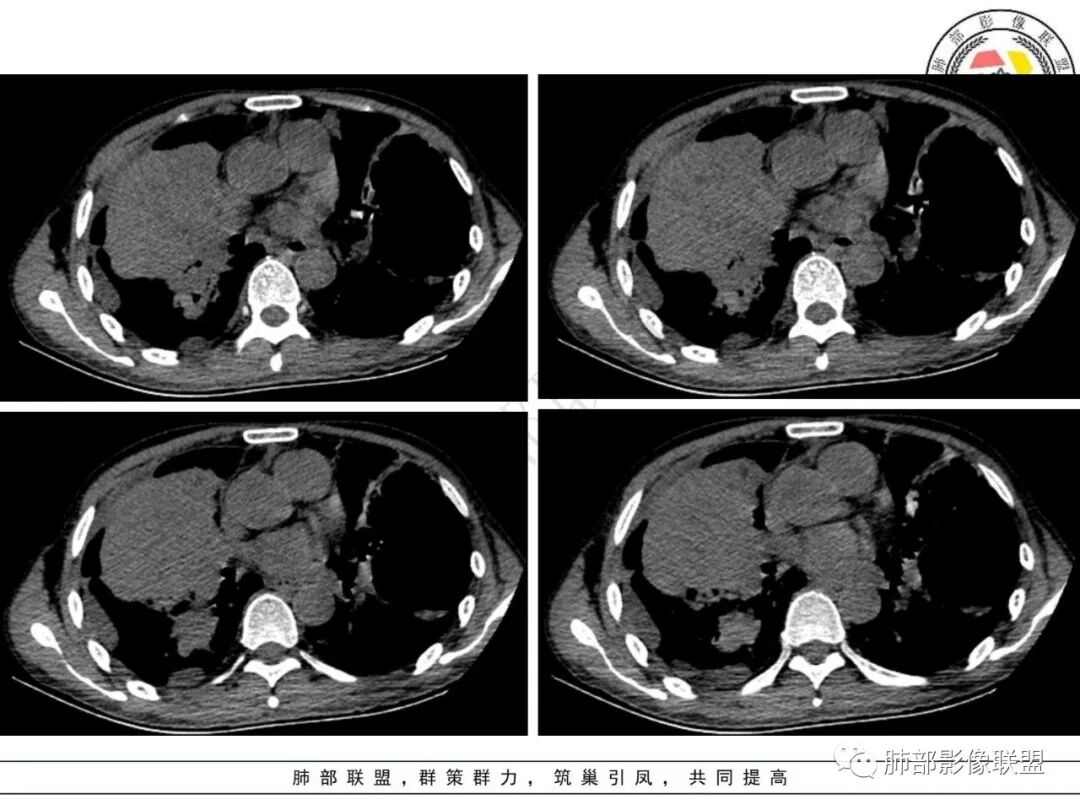

1.病例特点:中年男性,气促,中长病程。贫血明显,无发热。实验室轻度异常(C反应蛋白升高)。双肺多发结节、片状影,边界可分辨,多见支气管穿行,走形僵直。左肺上叶较大囊腔,腔内分隔明显,壁薄不均,可见结节样增厚,相邻肺组织膨胀不全。右肺上叶块影巨大,多支气管穿行,前段支气管闭塞,后段支气管扩张。余支气管管壁前段增厚。右上纵隔多发肿大淋巴结。右侧胸腔积液。

2.小结:临床病史及实验室检查与影像表现不相称,肺部块影及囊腔型病灶,应警惕新生物。右肺块影伴支气管闭塞,更多符合支气管肺癌等恶性肿瘤。

左肺囊腔性病灶,分隔,壁结节样增厚,也更符合恶性肿瘤,腺癌等为先。淋巴瘤可以,但并非常见。影像有时不宜越俎代庖,尤其是征象不够典型的,须结合病理检查。囊腔影较大时,邻肺膨胀不全应仔细甄别。